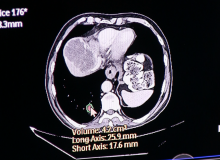

Using data from the world’s largest computed tomography (CT) dose index registry, researchers have established national dose levels for common adult CT examinations based on patient size. Healthcare facilities can optimize these exam protocols so that dose is commensurate with the size of the patient, avoiding unnecessary radiation exposure.